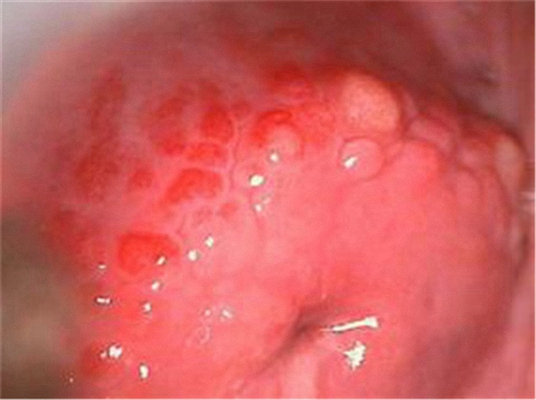

重度宮頸糜爛圖 (23)